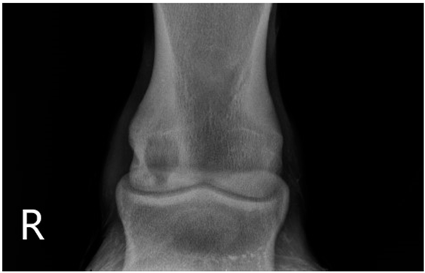

2.2. Image Analysis

Preoperative radiographs in DICOM format were evaluated blindly in a randomized order by three observers using medical imaging viewer software (OsiriX® Lite v12.0.1 DICOM viewer, Pixmeo SARL, Bernex, Switzerland). The width and height of the lesions were measured in dorsopalmar/plantar radiographic views. The magnification was corrected by calculating the index of the measured SCL with the total width of the specific joint affected. Each measurement was taken once by three authors. The mean of the three different measurements was calculated and used for statistical purposes. SCL shape was classified in three categories, following previous classification guidelines (Table 1 and Table 2) [8]. The intraclass correlation coefficient was calculated to make sure that there was a high level of agreement between observers when taking height and width measurements and when classifying SCLs by shape.

The median and interquartile ratios of the SCL height and width were 9.47 mm (6.97–10.92 mm) and 8.58 mm (6.98–10.96 mm), respectively. The SCLs located in the distal metacarpal/metatarsal bones measured 9.03 mm (6.96–10.9 mm) in height and 8.52 mm (7–10.92 mm) in width. A more oval shape was found in the lesions of the proximal phalanx, with a median height of 10.8 mm (7.03–10.95 mm) and a median width of 7.78 mm (7.09–10.96 mm). A rounder shape was found in the distal phalanx, with a median of 10.28 mm (7.05–10.97 mm) for height and 10.81 mm (7.03–10.95 mm) for width. The different bones affected by the SCLs were no different in the horse’s ability to start a race (p = 0.33).

Table 1. Radiographic appearance and shape classification into 3 types of subchondral lucencies based on their shape and communication with the joint.

Type 1Subchondral lucency with a dome shape and an articular surface defect of similar width as the middle of the lesion.Animals 13 02838 i001

Type 2Subchondral lucency with narrow communication with the joint surface (narrow cloaca) and round, wider lucency deeper in the bone.Animals 13 02838 i002

Type 3Subchondral lucency with no radiographic evidence of communication with the joint surface.Animals 13 02838 i003